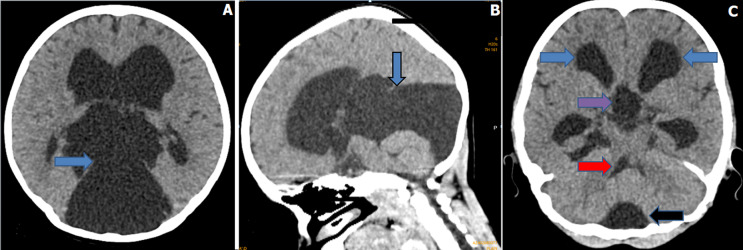

Unusual hydrocephalus from retrocerebellar arachnoid cyst sparing the fourth ventricle.